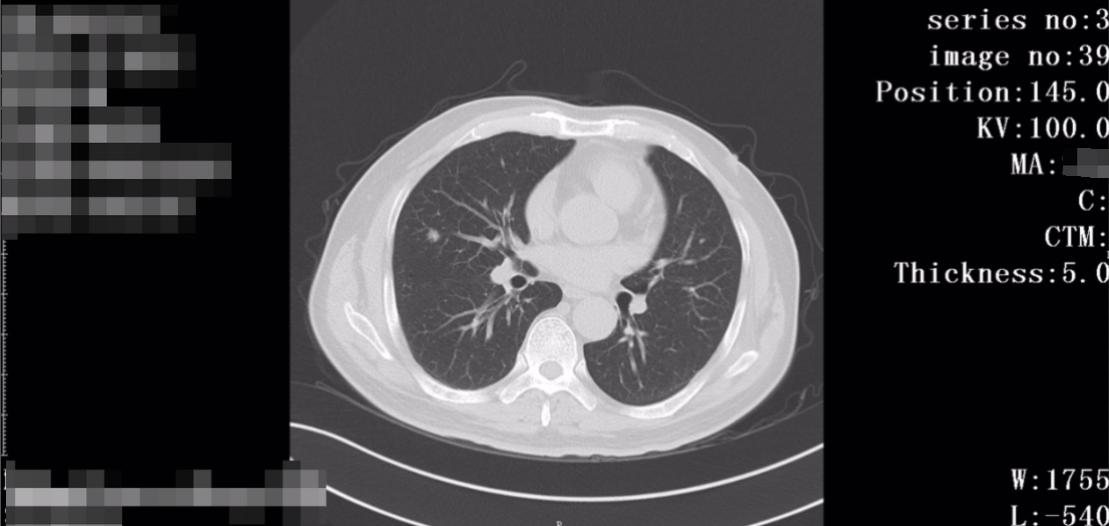

完善了相关检查,肺功能提示轻度功能障碍,可耐受手术, 胸部CT显示右肺中叶外侧段实性小结节影,约1.0cm*0.9cm,呈现浅分叶状,可见多发毛刺。

术后病理提示: (右上肺)原位腺癌,肺切缘净;(右肺中叶)浸润性腺癌(乳头状型约占90%,腺泡型约占10%)。

未见明确脉管癌栓及神经侵犯,无肺泡腔扩散,无胸膜侵犯。支气管残端、血管断端及肺切缘均干净,淋巴结未见癌转移,手术很成功,同时在早期Ia期切除,没有发现转移。

术后复查胸部增强CT显示右上肺结节切除术后改变。未见转移以及新发癌症,无明显异常。